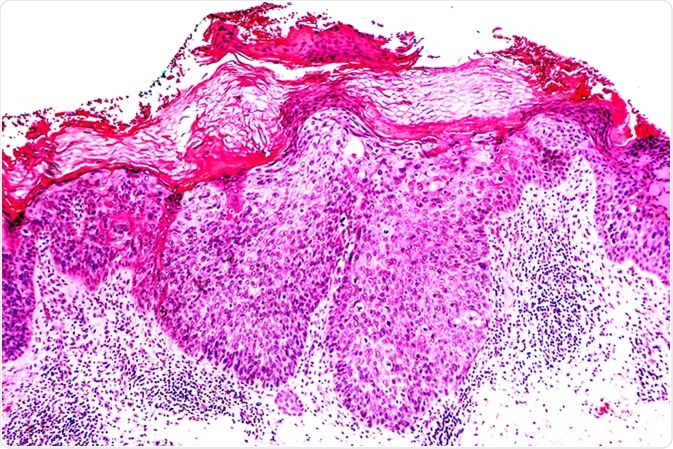

Cancer of Sun Damaged Skin: In squamous cell carcinoma in situ ("Bowen's disease"), malignant cells are confined to the epidermis, without invasion. Image Credit: David Litman / Shutterstock